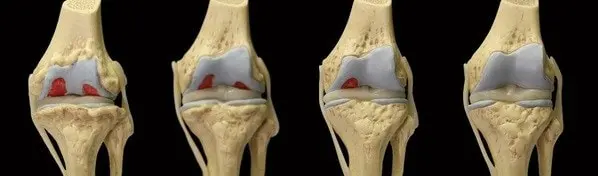

AVANT

APRÈS

Professeur Henry Bates : "Nous avons découvert que certains principes actifs pénètrent dans la nanostructure de l'articulation et stimulent la régénération des chondroblastes. Ils n'éliminent pas seulement les causes de l'inflammation, mais nourrissent également les cellules, déclenchant le processus d'auto-régénération. Les articulations rajeunissent littéralement. Ces principes actifs :

- stimule la régénération complète des chondroblastes - grâce à cela, les articulations se réparent indépendamment de l'âge

- augmente la quantité de liquide synovial de 40 % - cela rend les articulations plus fortes et plus élastiques

- élimine l'inflammation 9 fois plus rapidement - la douleur articulaire disparaîtra pendant la nuit